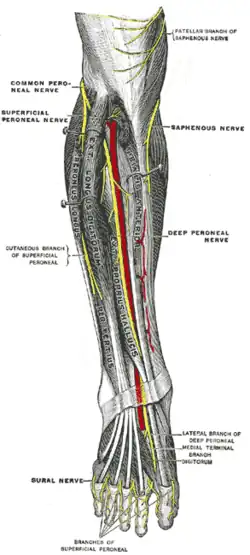

Diagramme de la distribution segmentaire des nerfs cutanés de la plante du pied. Nerfs profonds à l'avant de la jambe.

Nerfs profonds à l'avant de la jambe. Nerfs du dos du pied.